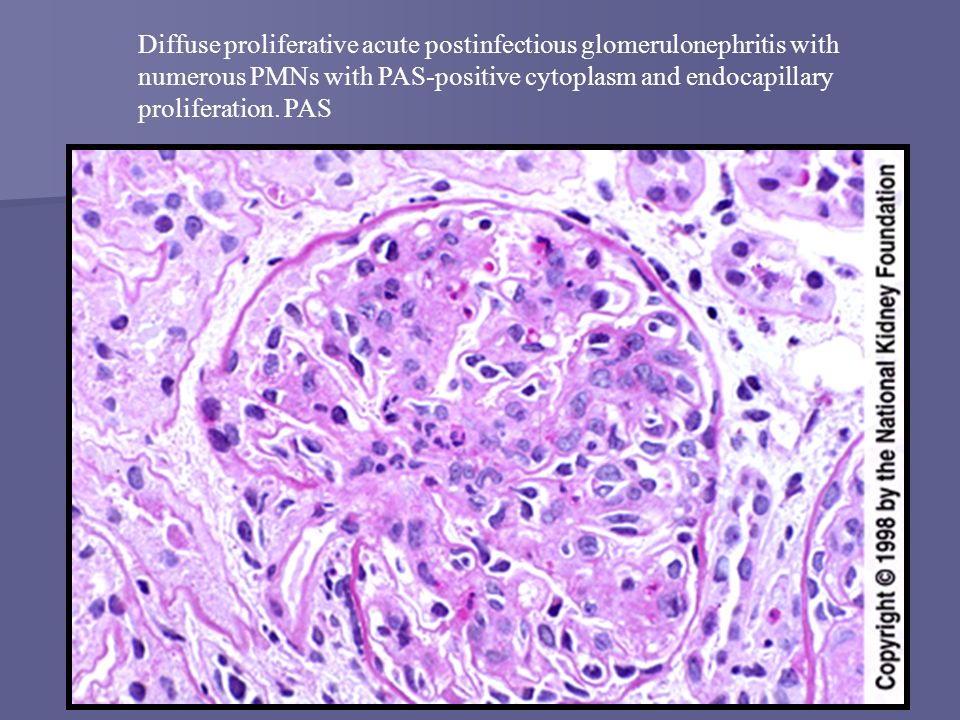

Симптомы подострого гломерулонефрита: фото и описание